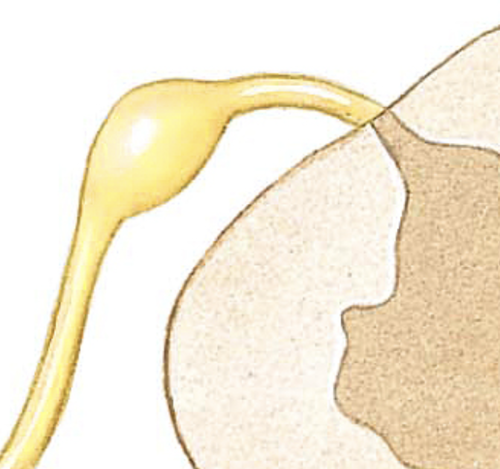

dura mater

pink layer

arachnoid mater

the light blue layer

subarachnoid space

The spaces between the purple/ The blue

pia mater

The first top layer/ under the purple stuff

The orange outer layer